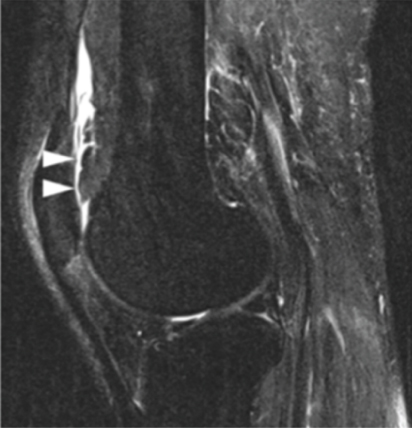

Simple radiographs showed no abnormal findings, and MRI images revealed a soft tissue mass located superolaterally to the PF joint that exhibited an ill-defined border with its surroundings. Both T1- and T2-weighted images at high signal intensities revealed the soft tissue mass, while low signal intensity was noted under fat suppression and no contrast enhancement was noted under contrast imaging (Figure 1). In addition, there were no abnormal findings in the blood examination.